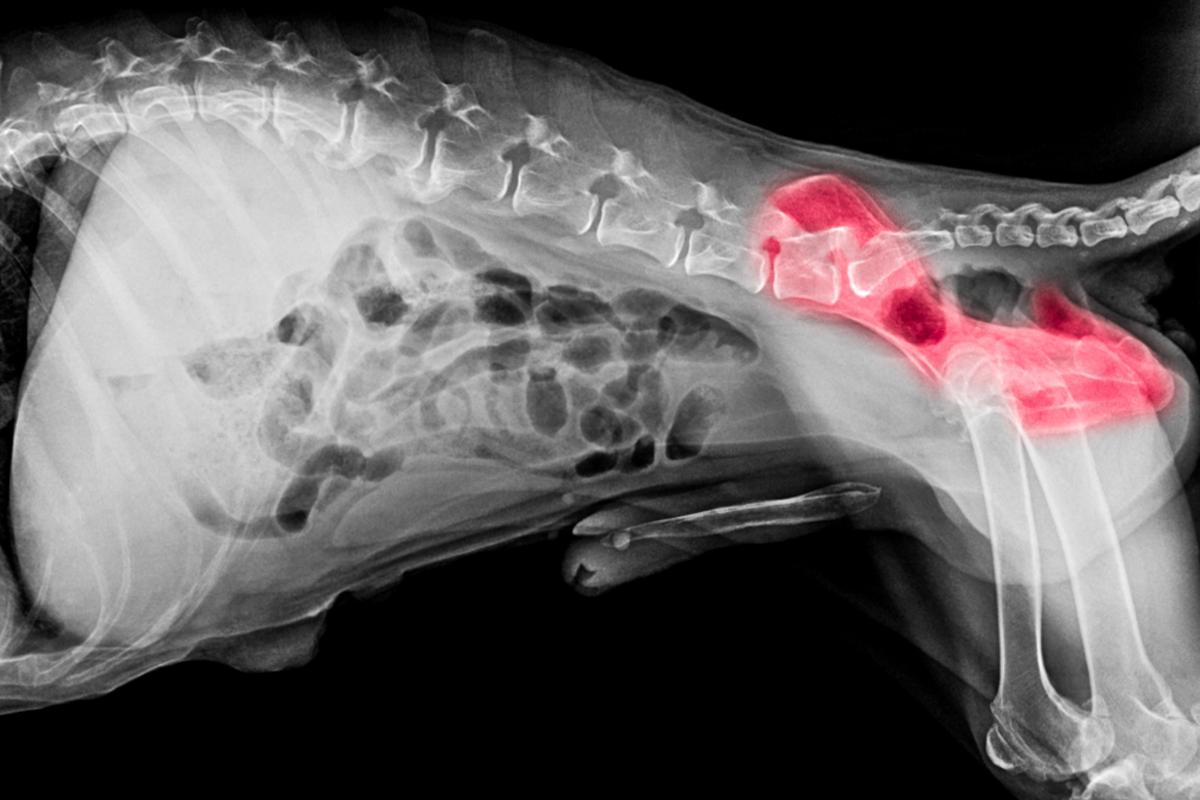

Displasias

A displasia do quadril e a displasia do cotovelo são doenças degenerativas e hereditárias do tipo osteoarticular e que geralmente afetam cães de raças grandes e gigantes. Quando a displasia está em estágio avançado, ela causa problemas significativos de mobilidade e mancadas persistentes, mas em estágios iniciais, pode resultar em mancadas mais leves e intermitentes. Portanto, é possível que um cão com displasia corra e brinque sem que possamos perceber claramente uma mancada, mas ela se torna mais evidente quando o animal está caminhando ou realizando algum movimento específico.

Além disso, no caso da displasia do quadril, os animais, principalmente os mais jovens, tendem a manter as patas traseiras juntas ao pular, o que faz com que pareçam dar "pulos de coelho" e tenham uma forma peculiar de sentar e deitar, o que pode sinalizar que algo não está bem.

A displasia pode ser controlada por meio de tratamentos e, em certos casos, pode ser corrigida com cirurgia.